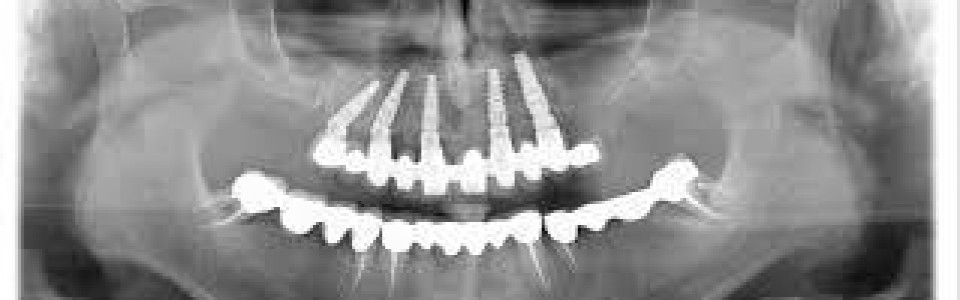

Implantologia 2

• Date: 5 Dicembre 2013